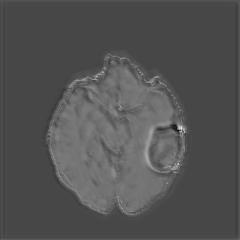

We argue that the sub-optimal paradigm of processing different abstractions within a single CNN pipeline can be remedied through the effective processing of information in a structured manner. Consequently, we devise strategies for disentangling the edge and texture information within a single training pipeline. Figure 2 illustrates how our proposed module, dubbed EG-CNN, can be paired with any existing CNN encoder-decoder to improve segmentation quality near intensity edges. We have applied our EG-CNN to the tasks of brain and liver tumor segmentation in medical images (Figure 3).

(1) Brain MR (2) Liver MR (3) Liver CT (4) Lung CT